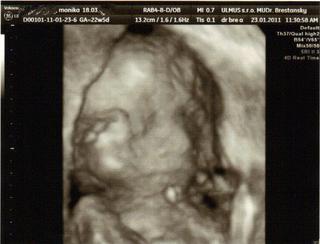

dnes sme boli na tom 4D... no naša malá potvora sa nám ukázala iba na malinkú chvíľočku a potom ani za nič 😀

tak o 2 týždne ideme zasa ale už ju nebude merať už iba kvôli videu aby sme mali peknučké lebo teraz nie je skoro nič v 4 D , lebo to nebolo riadne vidieť.. Keď to mmm donahráva na youtube hodím vám sem link.. malo by to ešte takých 20 minút trvať.

Malinká je krásna a váži cca 572 g 😀 Zodpovedáme 23 tt a 2 d.. sme 22 tt a 5 d... takže je to ok 🙂

STále mala ručičku pred tváričkou 😀

@alena24 - vidím, že váš je ako naša .-D tiež tie ruky pred tvárou. ale aspoň zo začiatku na chvíľu ukázala.. 😀